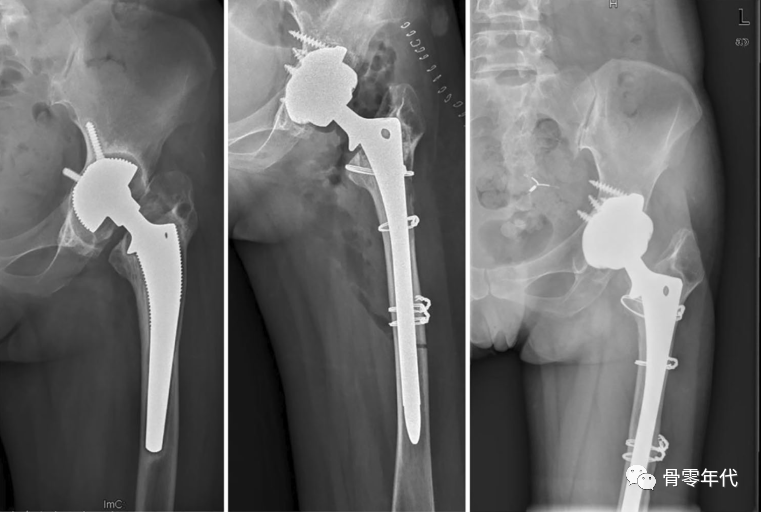

应用多孔钽假体重建Paprosky 3A缺损术的一例(左侧髋关节)的X线片:术前(左)、术后(中)和10年后(右)的正位X线片

加强螺钉固定